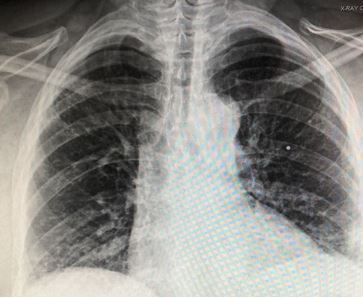

History of present illness: A woman in her mid-50’s with a history of rheumatoid arthritis presents to the hospital for 3 days of pleuritic left upper back pain without fever, shortness of breath, chest pain or cough. She also denies any injury and has not had this pain previously.

Vital signs & physical examination. Vital signs are normal except for a pulse oxygen level of 94% on room air. Physical exam is otherwise normal except for bilateral rales heard only with deep breathing.

Imaging: Chest x-ray, image below